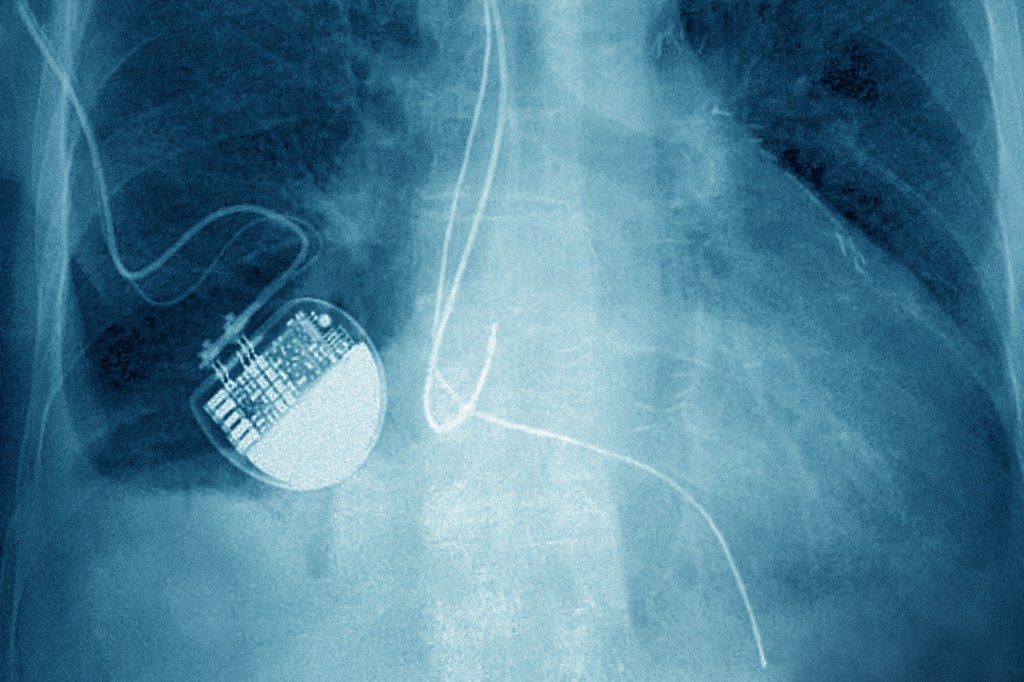

an X-ray of a pacemaker

Image Credits:Getty Images